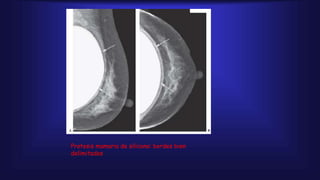

Protesis mamaria de silicona: bordes bien

delimitados